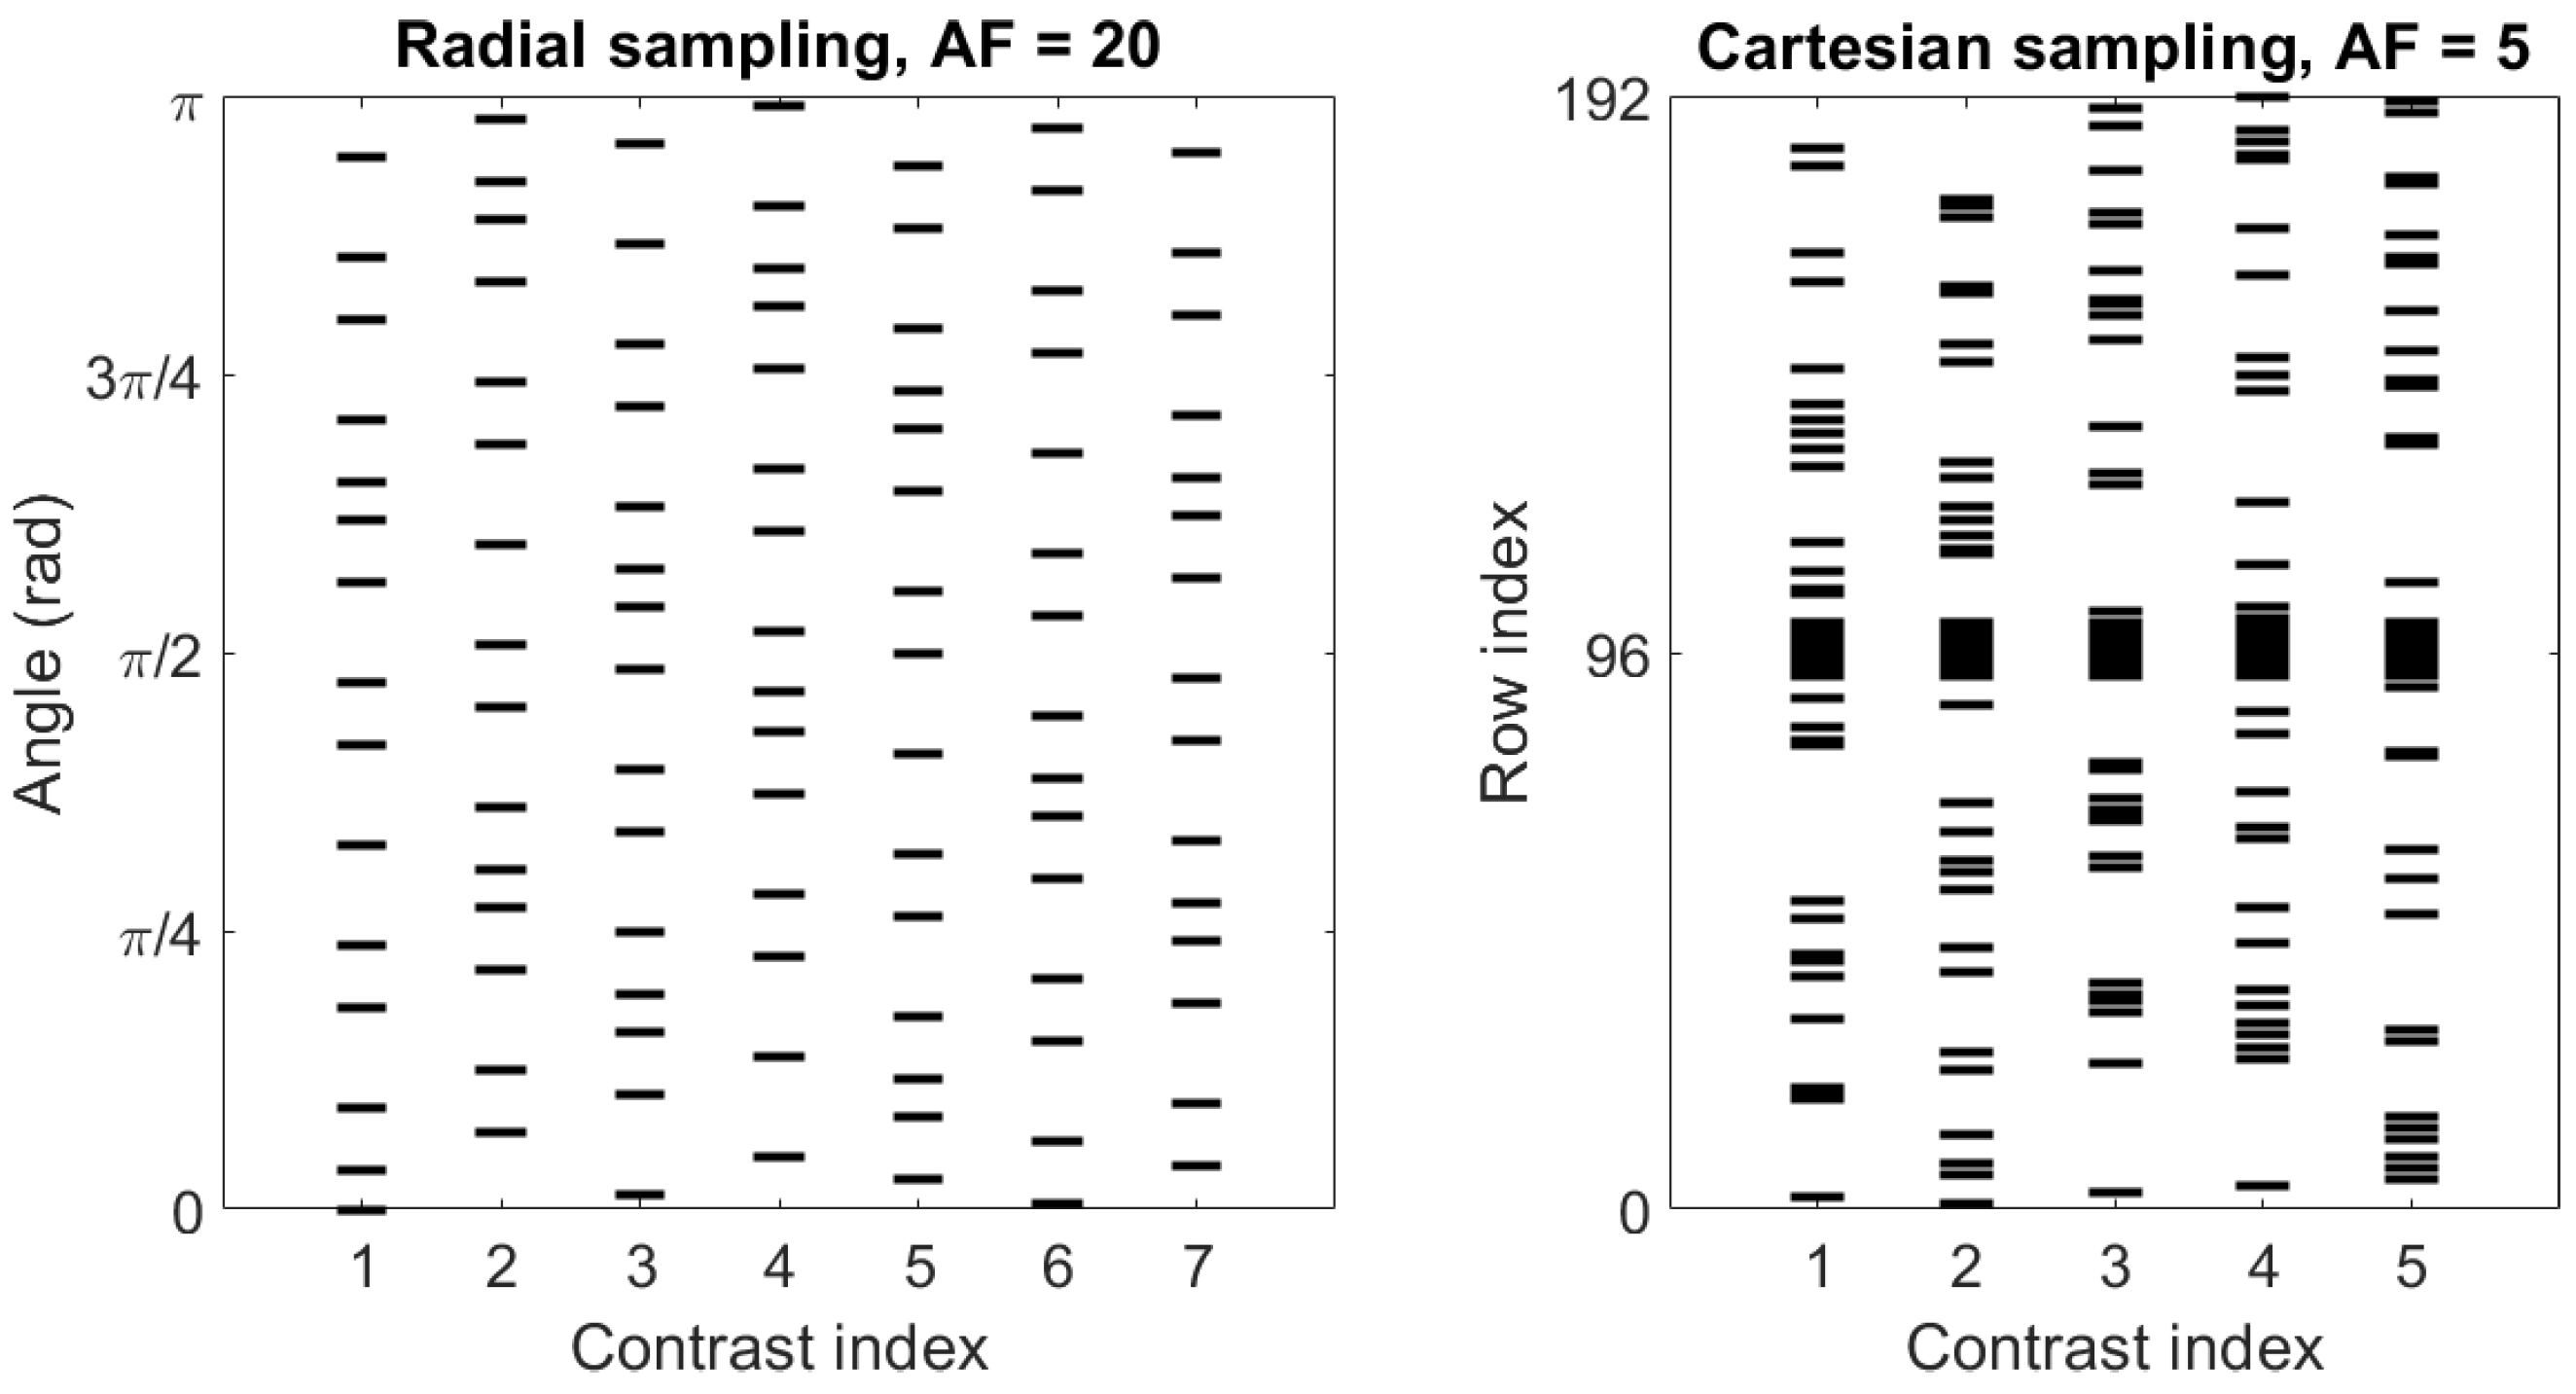

3.1. Simulated Golden Angle Radial Data

3.2. Cartesian Data from Ex Vivo Mouse Kidney

3.3. Reconstruction Specifics